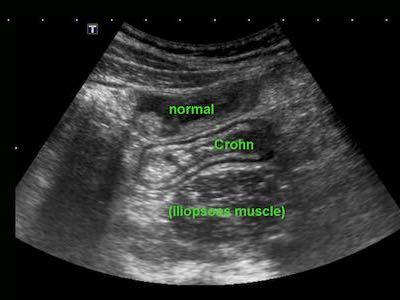

Sự khác biệt về kích thước và khả năng bị ép xẹp của hồi tràng bình thường (bên trái) và hồi tràng bị tổn thương do Crohn trong quá trình ép dần từng bước.

Sử dụng kỹ thuật ép dần từng bước, hai đoạn ruột kề nhau được ép vào cơ thắt lưng chậu.

Đoạn ruột phía trước là bình thường và dễ dàng bị ép xẹp, trong khi quai ruột bị Crohn hầu như không thể bị ép xẹp.